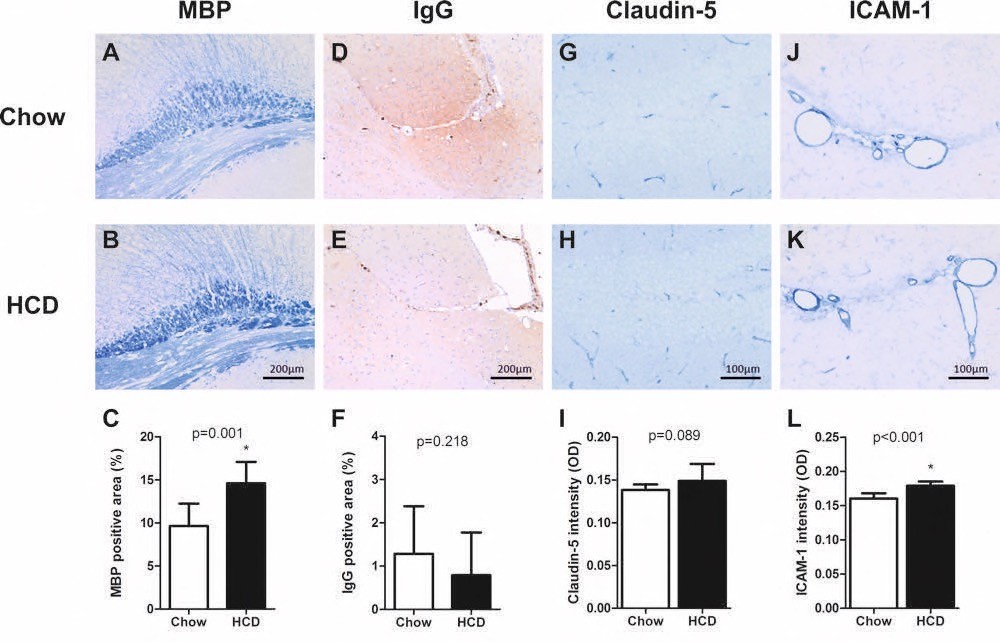

Chapter 5 Figure 4Histological cerebral changes in ApoE*3L.CETP mice on HCD. Representative images and statistics are shown of white matter marker MBP (A-C), BBB leakage marker IgG (D-F), tight-junction marker Claudin-5 (G-I) and endothelial activation marker ICAM-1 (J-L) analyses in ApoE*3L.CETP chow fed mice (A, D, G, J) compared to HCD mice (B, E, H, K). x p<0.05.